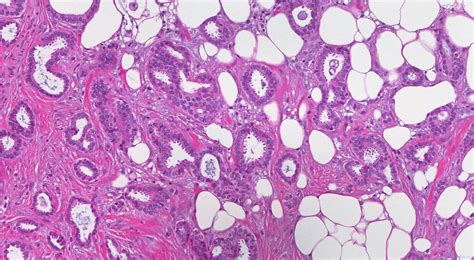

Invasive carcinoma of the left breast , also known as infiltrating carcinoma, is a type of breast cancer that has spread from its original location in the milk ducts or lobules into the surrounding breast tissue. This is in contrast to in situ carcinoma, which remains confined to its original location. Understanding the nuances of this condition is essential for accurate diagnosis, treatment planning, and, of course, proper coding using the International Classification of Diseases, Tenth Revision (ICD-10).

The diagnosis of invasive carcinoma typically involves a combination of physical exams, imaging studies (like mammograms, ultrasounds, and MRIs), and a biopsy. Once invasive carcinoma is confirmed, doctors will determine the stage and grade of the cancer. Staging refers to the extent of the cancer’s spread, while grading describes how abnormal the cancer cells look under a microscope. These factors play a crucial role in determining the best course of treatment, which may include surgery, radiation therapy, chemotherapy, hormone therapy, and targeted therapies.